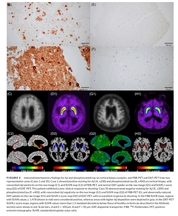

HER2 양성 위암 치료에서 기존 표적치료제에 다른 표적치료제를 같이 사용하자 치료 효과가 높아졌다는 전임상 연구 결과가 나왔다. 분당서울대병원 혈액종양내과 이근욱 교수팀(강민수 교수, 의생명연구원 김귀진 박사) 연구에 따르면 HER2 양성 위암세포를 이식한 쥐에 트라스투주맙 데룩스테칸(엔허투)과 퍼투주맙(퍼제타)을 함께 투여하자 종양 크기가 효과적으로 감소한 사실이 확인됐다. HER2 양성 위암은 세포 성장과 분열을 촉진하는 HER2 단백질이 과다 발현돼 생기는 암이다. 위암 환자의 약 20%에서 나타나며, 암의 성장과 전이가 촉진돼 평균 생존기간이 16~20개월 정도로 짧은 편이다. HER2 양성 위암 치료는 표적치료제인 트라스투주맙 데룩스테칸을 사용한다. 표적치료제란 암세포의 분자나 단백질 등을 정밀하게 타격하는 약제로 정상세포까지 공격하는 기존 항암제보다 효과는 뛰어나면서 부작용은 관리하기 쉽다. 트라스투주맙 데룩스테칸은 암세포 표면의 HER2를 찾아가 항암제를 직접 투하하는 기전으로 작용한다. 하지만 표적치료제도 여러 환자에서 치료 효과가 떨어지거나 치료 과정에서 내성이 생기는 사례가 종종 있었다. 이는 HER2 암세포가 생존하기 위해 HER3라는